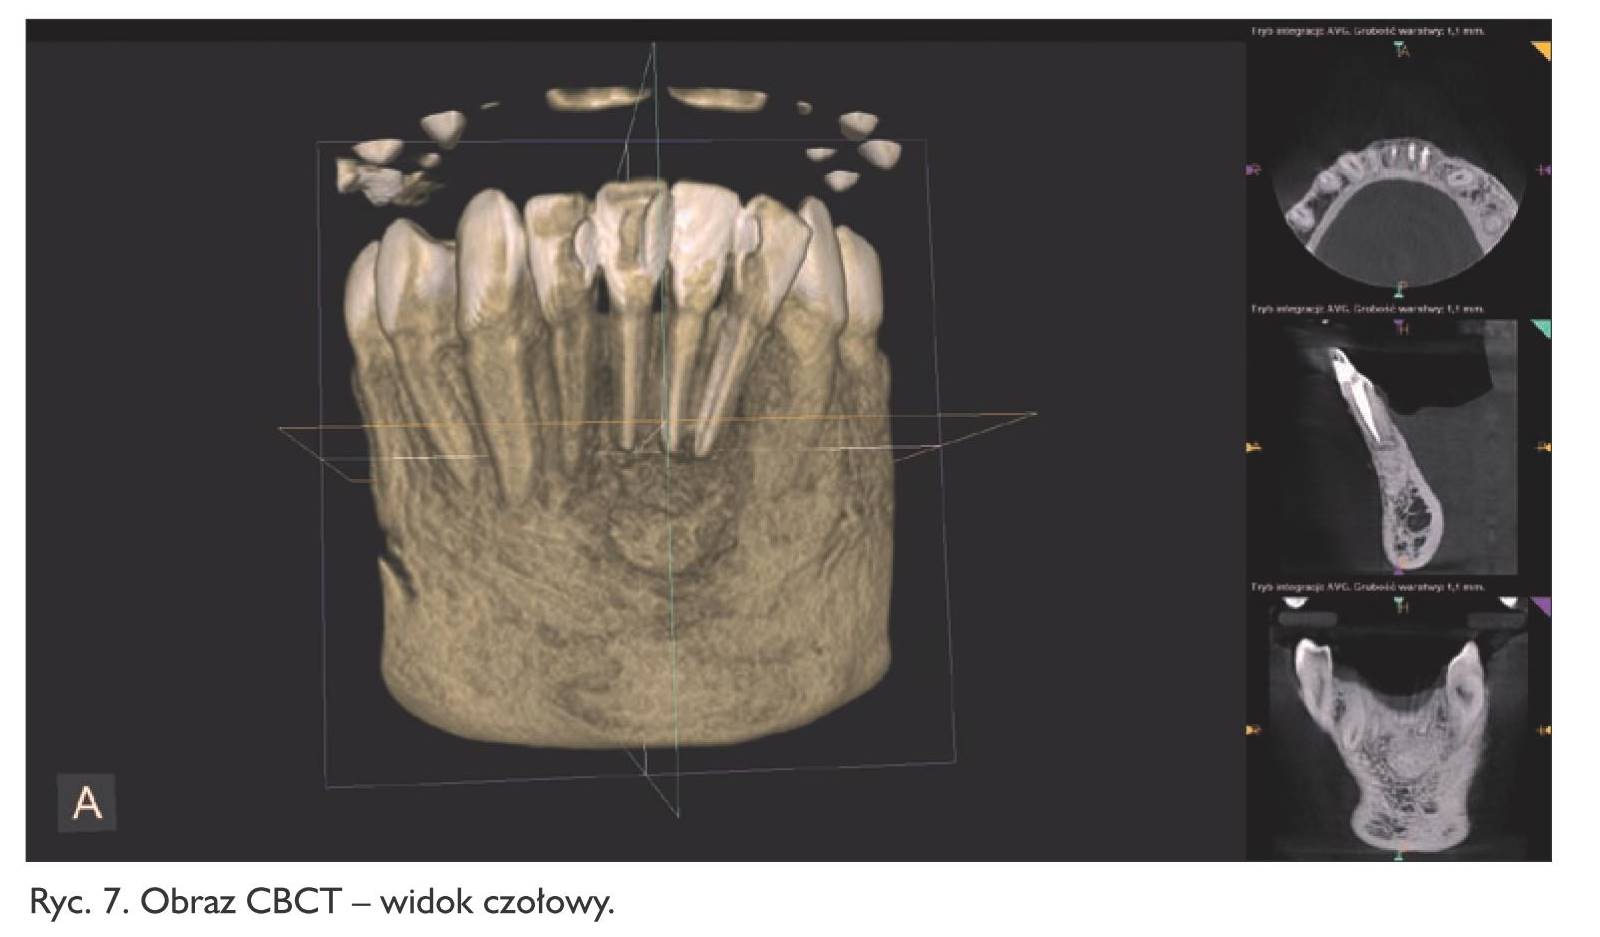

Pacjent zgłosił się ponownie dopiero po roku!, w marcu 2015 roku (pracował za granicą). Dolegliwości ustąpiły, aczkolwiek odczuwał pewne „drętwienie” tej okolicy. Zęby ponownie otwarto, wypełniono kanały metodą kondensacji bocznej gutaperki, zamknięto płynnym kompozytem oraz szkło‑jonomerem i wykonano badanie tomografii komputerowej wiązki stożkowej tej okolicy (ryc. 2, 3, 4), które ujawniło duży ubytek kostny okolicy wierzchołków korzeni zębów 32, 31, 41 z utratą blaszki wargowej części zębodołowej żuchwy, odpowiadający obrazowi torbieli korzeniowej.

Pacjent zgłosił się po tygodniu w celu usunięcia szwów. Rana goiła się prawidłowo. W opisie badania histologicznego wysłanego materiału potwierdzono wstępną diagnozę cystis odontogenes. Kontrolne badanie tomograficzne wykonano po  6 miesiącach, wykazało ono pełną odbudowę kostną ubytku (ryc. 6, 7, 8, 9). Pacjent od czasu zabiegu nie odczuwał żadnych dolegliwości w tej okolicy.